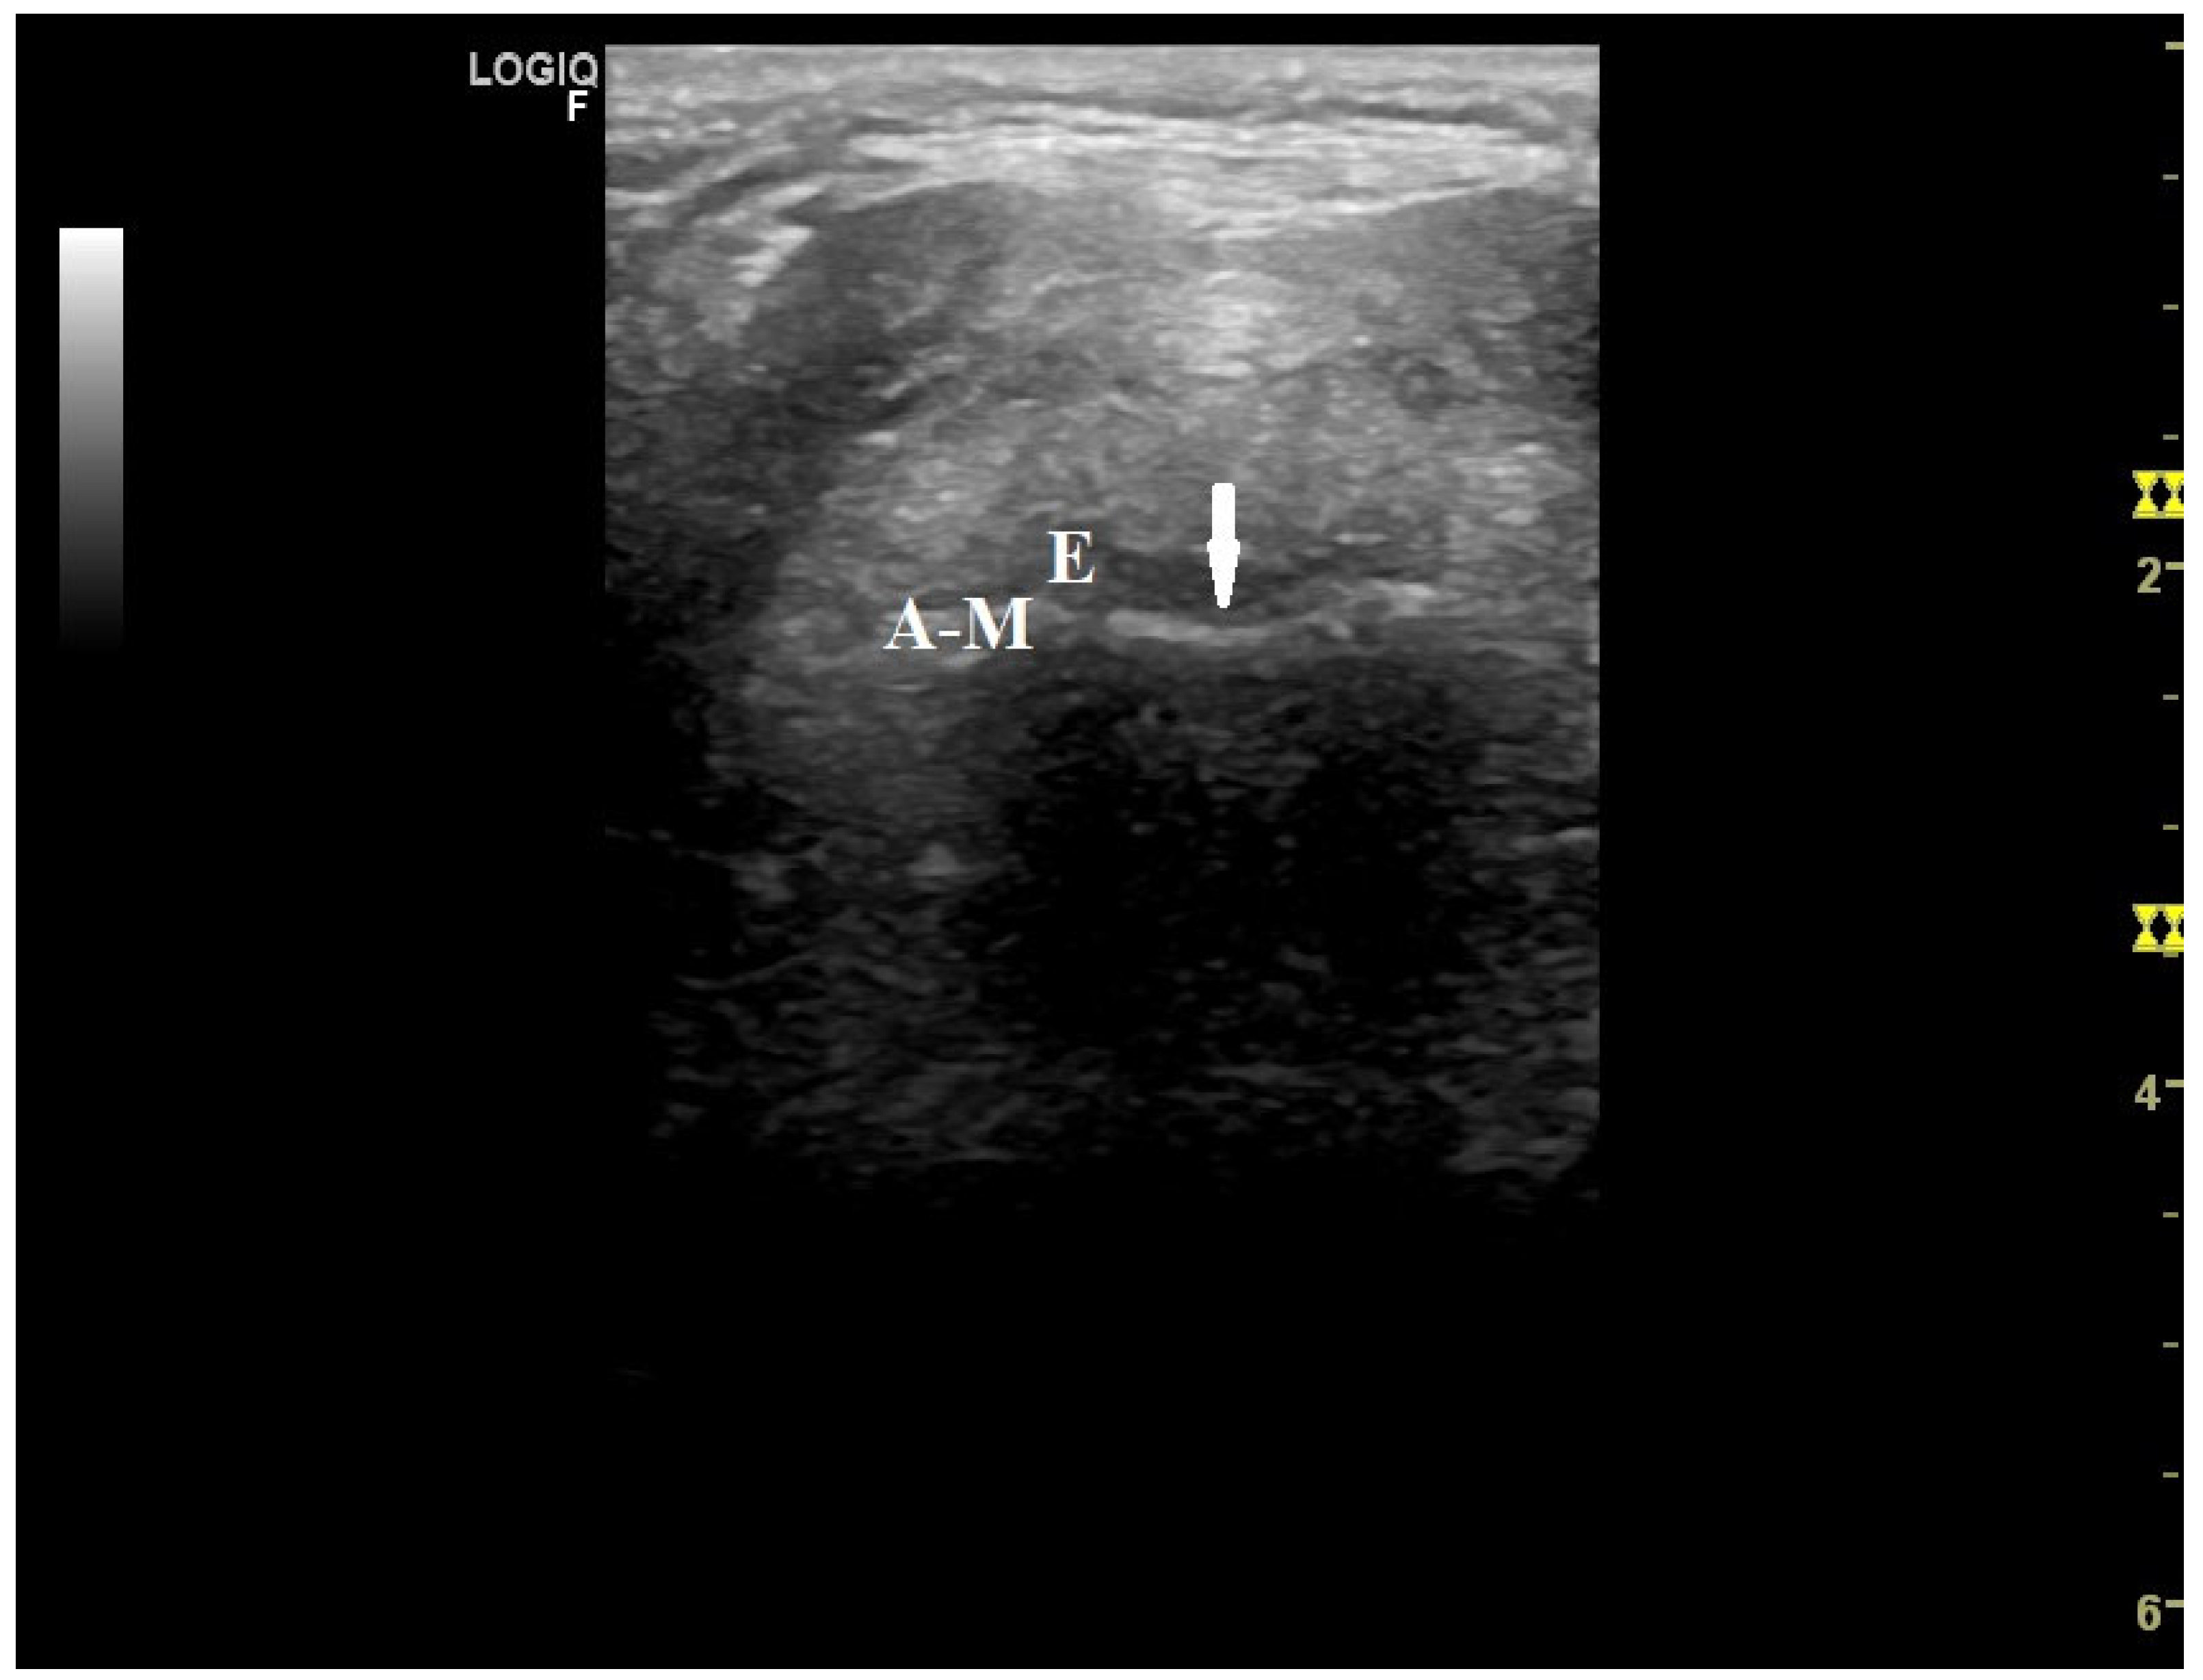

- Brekka, A.K.; Vollsæter, M.; Ntoumenopoulos, G.; Clemm, H.H.; Halvorsen, T.; Røksund, O.D.; Andersen, T.M. Adjustments of non-invasive ventilation and mechanically assisted cough by combining ultrasound imaging of the larynx with transnasal fibre-optic laryngoscopy: A protocol for an experimental study. BMJ Open 2022, 12, e059234. [Google Scholar] [PubMed]

- Andersen, T.; Sandnes, A.; Brekka, A.K.; Hilland, M.; Clemm, H.; Fondenes, O.; Tysnes, O.B.; Heimdal, J.H.; Halvorsen, T.; Vollsæter, M.; et al. Laryngeal response patterns influence the efficacy of mechanical assisted cough in amyotrophic lateral sclerosis. Thorax 2017, 72, 221–229. [Google Scholar] [PubMed]